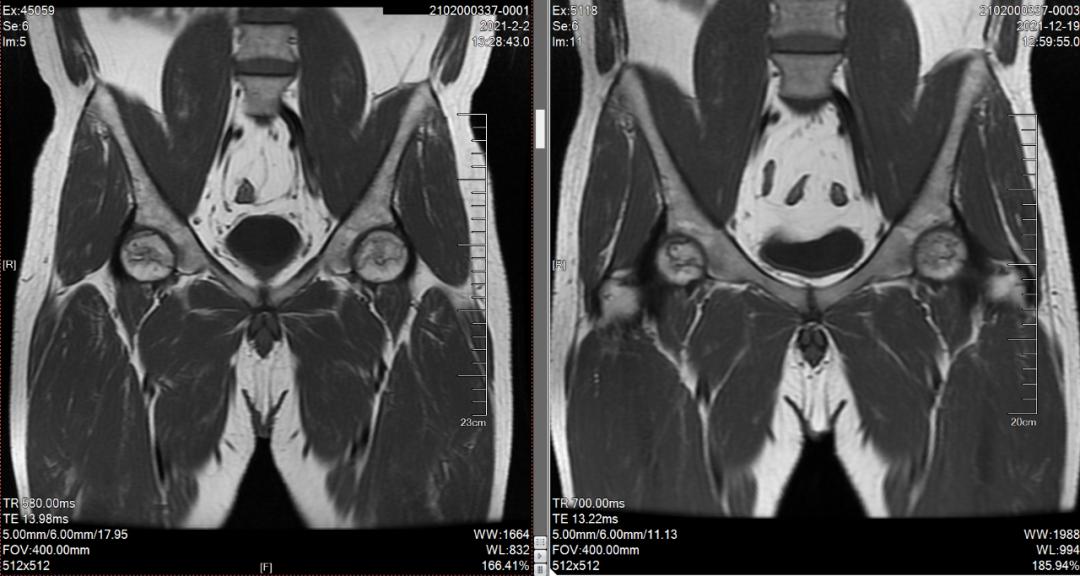

“我看过很多医生,你们的非手术保髋真的有效果吗?”这是小王在住院期间常对康复治疗师和医生说的话。没想到住院快要结束时,小王的疼痛就缓解了不少,这让小王惊喜不已,他开始认可三院非手术保髋的疗法。出院后小王又按照何伟教授的要求,认真拄双拐、坚持服药,三月后复查的磁共振、X光显示病情比较稳定,他便预约第二次入院治疗,经过半年时间的治疗,现在小王已经基本恢复了正常生活。

△治疗前后X光片、磁共振对比可见:双侧股骨头坏死修复,未发生塌陷,病情稳定